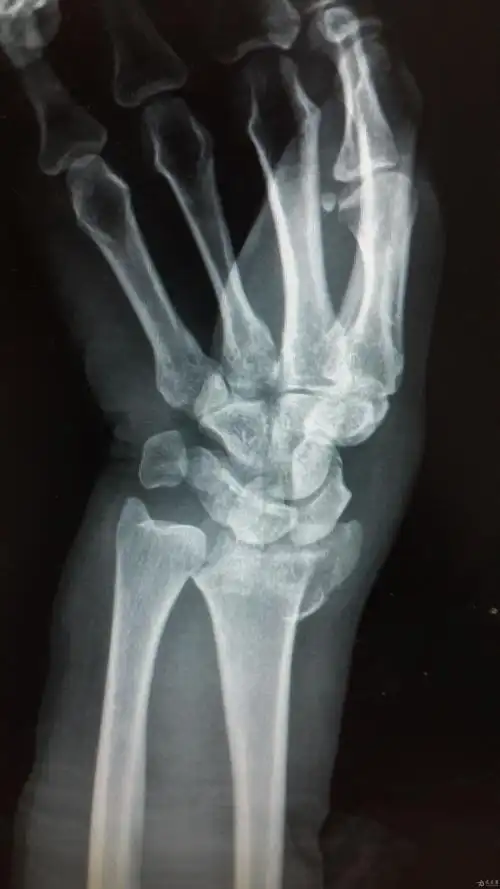

左陈旧性colles骨折一例